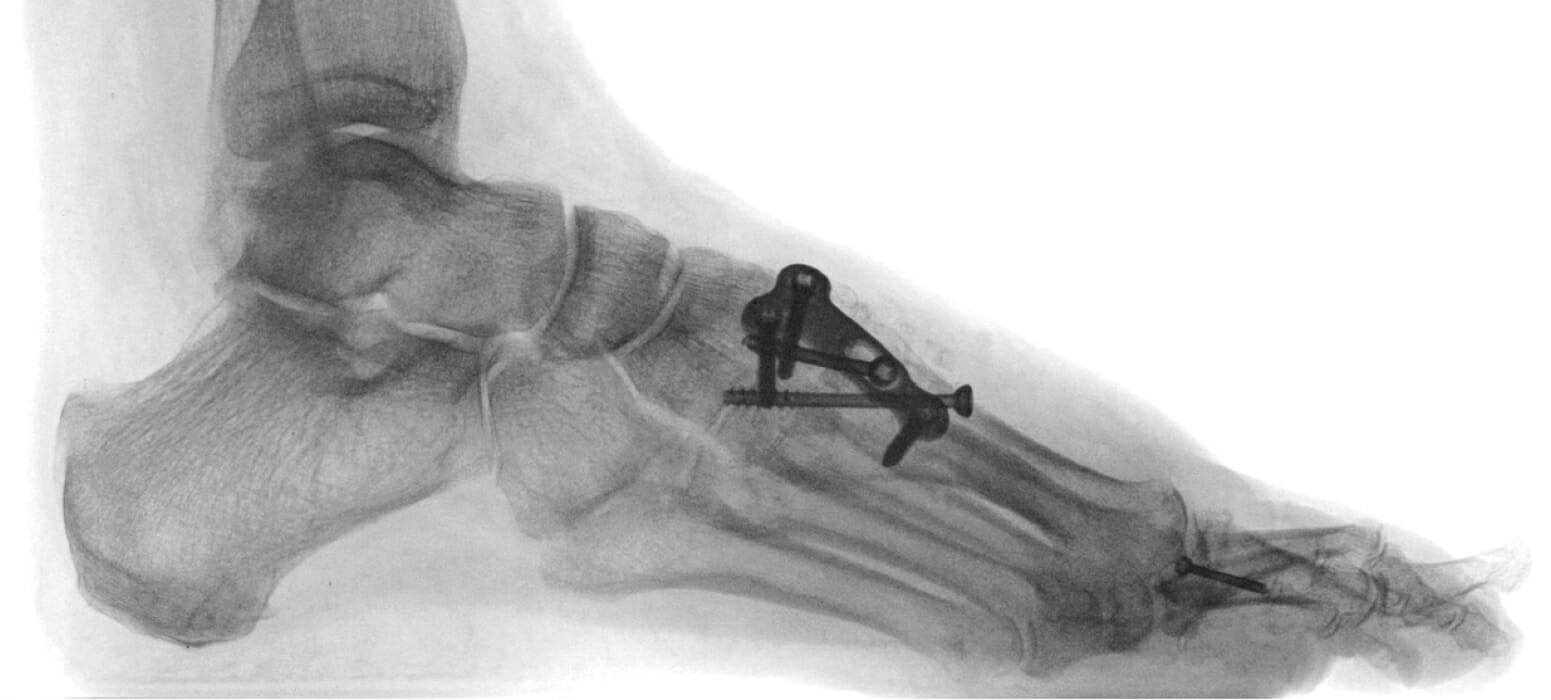

Source: guessrmcg.pages.dev Plattfuß Hilfe bei Schmerzen durch eine aufliegende Fußsohle Liebscher & Bracht , Operative Korrekturen von Fuß und Sprunggelenk beinhalten regelmäßig Durchtrennungen und Verschraubung von Knochen zur Stellungskorrektur des Fußes Diese Prozedur erfordert meistens einen speziellen chirurgischen Eingriff, der im Vergleich zur Osteosynthese relativ kurz ist.

SchraubenausdreherAnleitung » So entfernen Sie festsitzende Schrauben . Eine mögliche Ursache für Fußschmerzen sind Schrauben, die im Rahmen einer Osteosynthese eingesetzt wurden Damit der Knochen in der korrigierten Stellung verheilt, werden Platten und Schrauben zu Stabilisierung eingebracht.

Source: prozapksu.pages.dev Hallux valgus Behandlung und Operation Orthopädie Zentrum Arabellapark München , Schmerzen im Fuß können sehr unangenehm sein und verschiedene Ursachen haben Nach der Osteosynthese werden die Drähte, Schrauben und Platten schonend entfernt